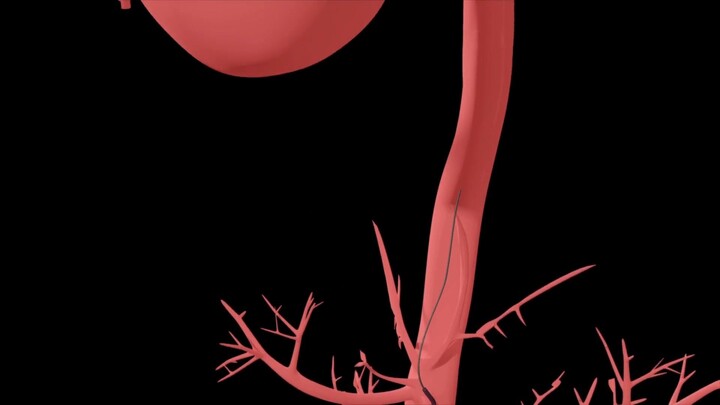

Son bioinfo-presentaciones en credit´s de imagen Flexibilidad (permanencia, resistencia, estabilidad, facilidad o soporte) de diagnóstico que sigue en